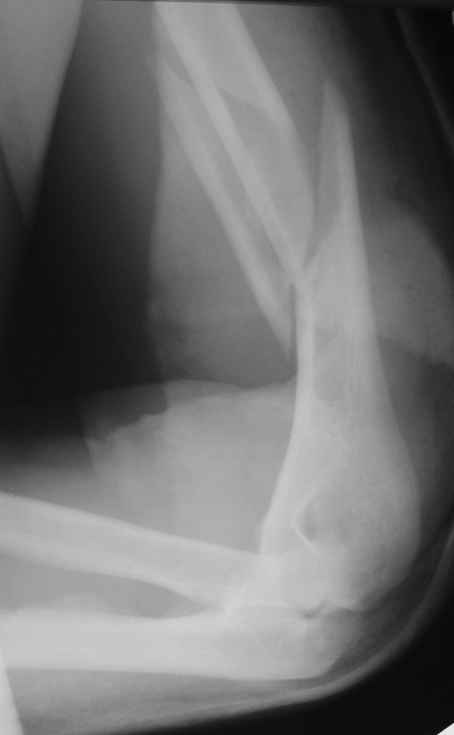

>антероградный - 30 процентов имеют боль в плече, связанную с повреждением ротаторной манжеты

Мы в последние годы все еще используем для переломов такой локализации эластичные титановые стержни (по мотивам ярославских разработок, Зверева-Ключевского). Такой стержень можно вводить не через сухожилие надостной мышцы, а дистальнее.

Снимки до, через 1 и 2 мес. после синтеза.